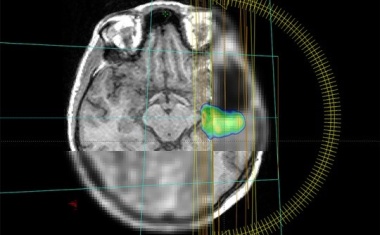

Mit 1,2 Mio. Euro fördert die Europäische Union ein internationales Projekt unter Leitung des Universitätsklinikums Freiburg zur Bestrahlung gefährlicher Hirntumore.